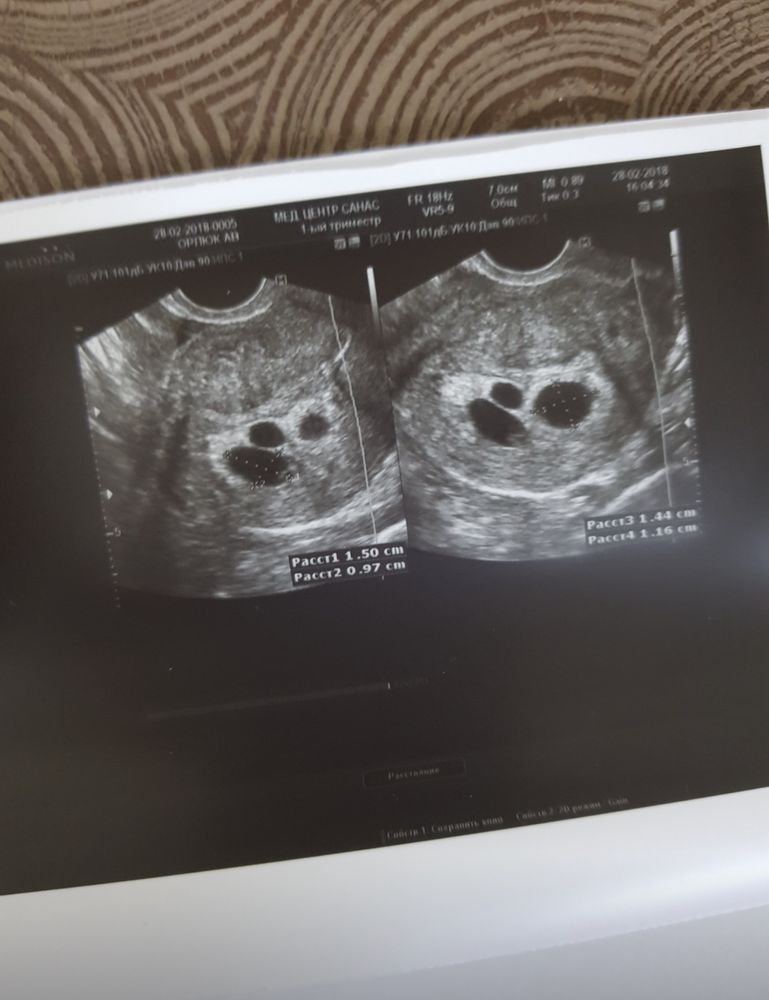

Была в успешном протоколе интересная штука, был перенос 2х картошек и одна из них поделилась на 2, потом в самом большом плодном яйце эмбрион так и не появился. И в паре (пятидневки, которая разделилась) 1 сердечко забилось. Это просто чудо какое то было. Половину беременности просто молилась каждый день, чтоб с оставшимся все было ок.